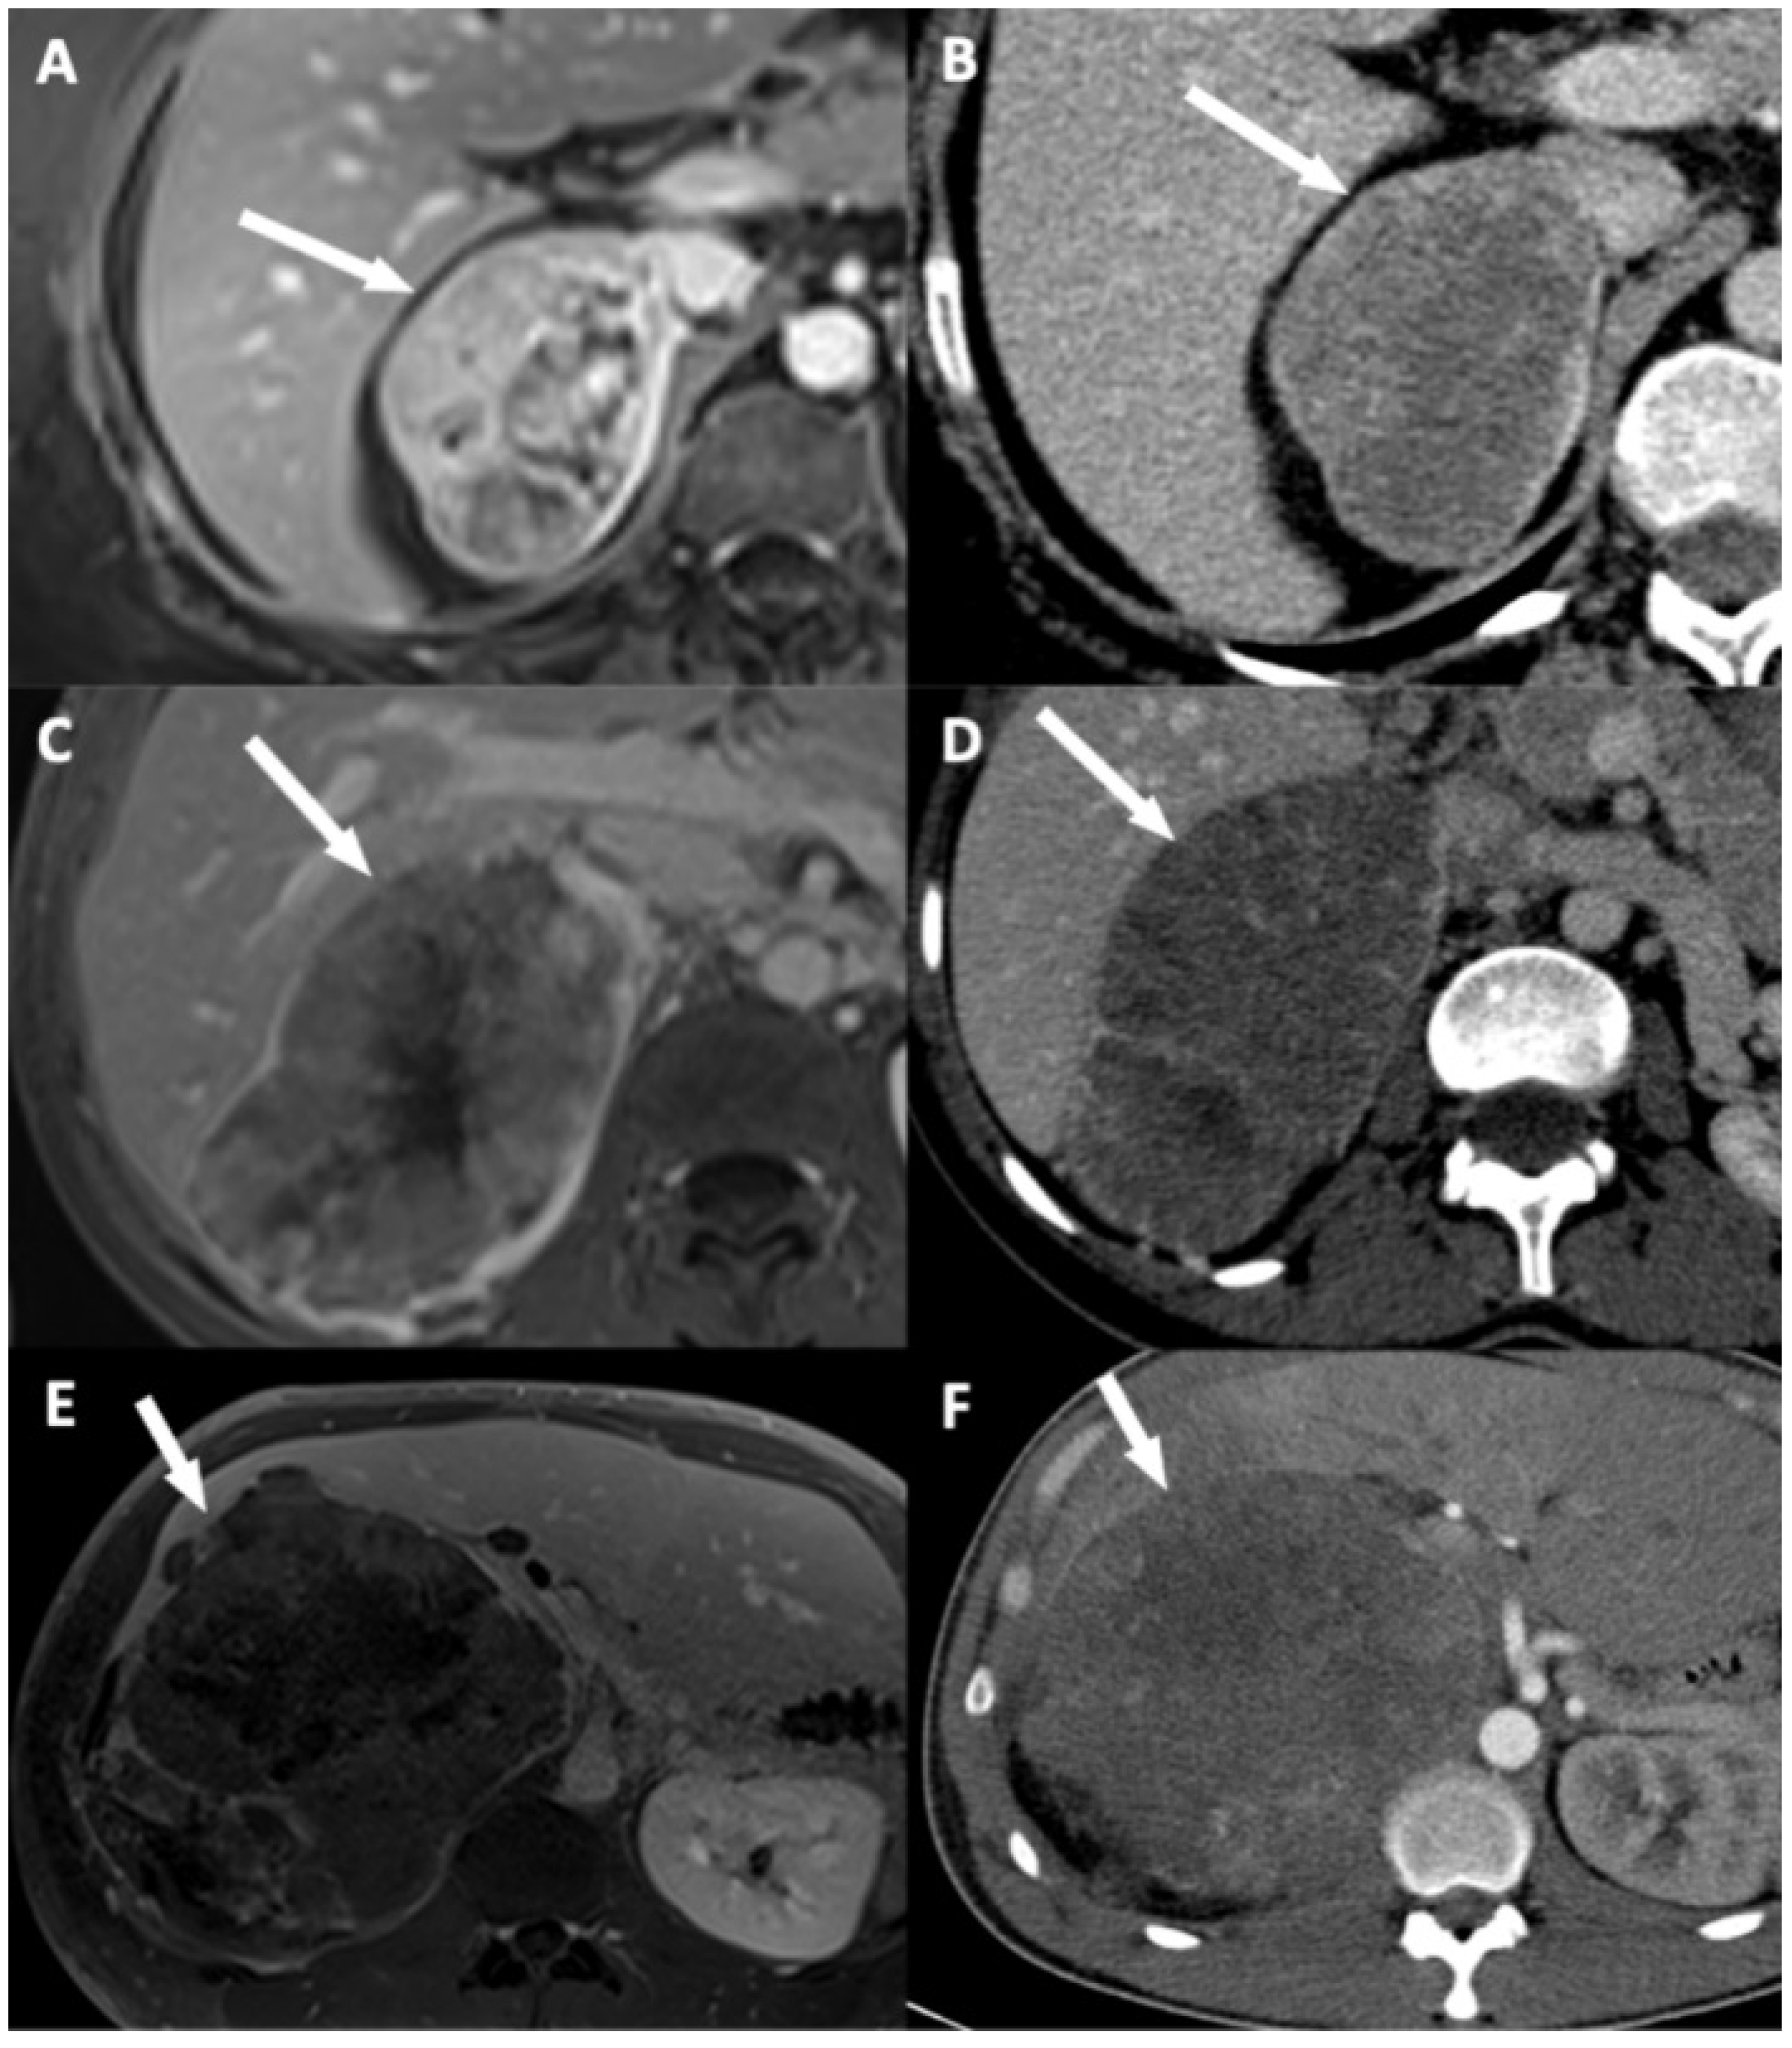

3.3. Qualitative Findings

| Disappearance of fat border between ACC and liver | Portal phase CT T2 HASTE MRI (**) | Fat border between ACC and liver non-measurable (<1 mm) |

| ACC contour disruption | Portal phase CT Portal phase MRI | Measurable adrenal capsular defect without any enhancement |

| Focal ACC bulge | Portal phase CT Portal phase MRI | Focal and abrupt irregularity of ACC shape |

| Periadrenal fat densification | Portal phase CT T2 FSE MRI | ΔHU between periadrenal fat and normal retroperitoneal fat >10 HU Hyperintense areas in the periadrenal fat |

| Macroscopic mass effect on inferior vena cava | Portal phase CT Portal phase MRI | Intrahepatic displacement of the vessel and direct contact with the tumor ± changes of its caliber |

| Macroscopic mass effect on right hepatic vein | Portal phase CT Portal phase MRI | Intrahepatic displacement of the vessel and direct contact with the tumor ± changes of its caliber |